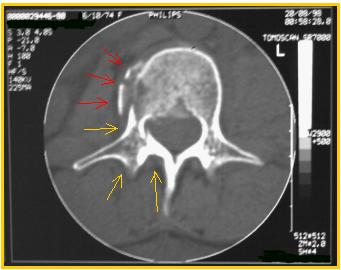

| In una sezione TAC più caudale del soma di L2 si osserva l'estensione inferiore della frattura che coinvolge esclusivamente il soma nella porzione laterale (freccie rosse). Peduncolo e arco posteriore si confermano integri (freccie gialle). La TAC è un esame bidimensionale, tuttavia il piano su cui vengono acquisite le immagini - quello trasversale - è proprio quello non ottenibile con le normali radiografie standard. Inoltre, l'ottima visualizzazione del tessuto osseo lo rende ideale per valutazioni in campo traumatologico. |  |